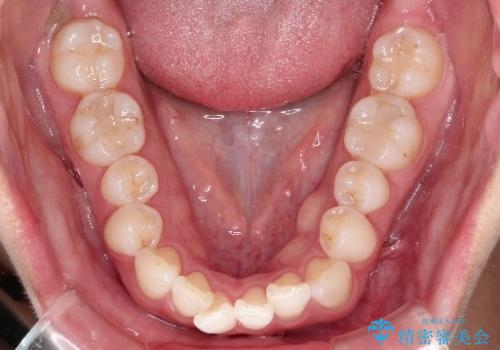

初診時の歯並びの状態としては、下顎前歯に及ぶの中等度のがたつき(叢生)があり、前歯が深く噛みこんでいる状態でした。

抜歯は行わず歯列弓の拡大やディスキング(歯と歯の間の隙間を作る処置)を行い叢生を改善しました。